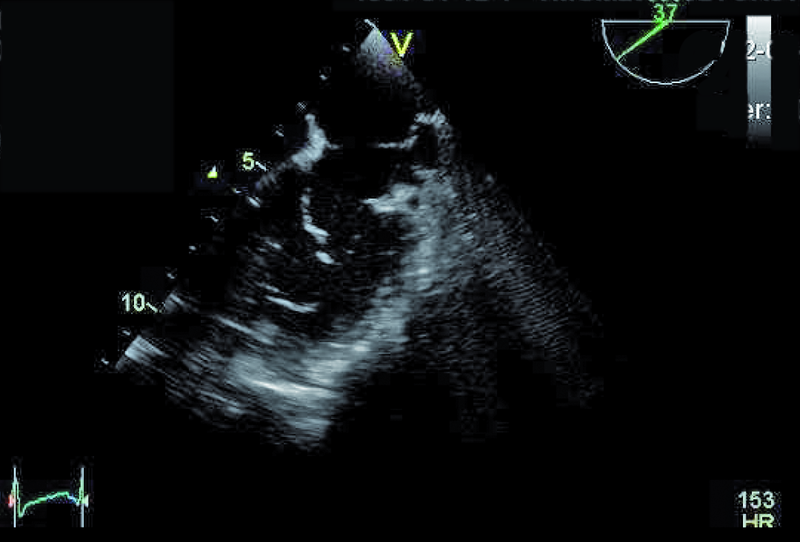

Przedstawiona chora, prawie dorosła kobieta, znajduje się w tej drugiej grupie. Jamy serca są u niej niepowiększone, a mięsień ma prawidłową grubość (ryc. 1). Rozpoznanie membrany w jamie lewego przedsionka z prawidłowym obrazem zastawki mitralnej nie nastręcza trudności. Membranę można dostrzec w wielu projekcjach (ryc. 2-4). Badanie przezprzełykowe pozwala na bardziej precyzyjne określenie średnicy otworu, która zazwyczaj waha się od kilku milimetrów do centymetra. W omawianym przypadku otwór jest duży i na podstawie samej jego wielkości można przypuszczać, że nie powoduje obstrukcji przepływu (membrana w projekcji na rycinie 4 znajduje się powyżej zastawki). Tryb doplera ciągłego (ryc. 5) także nie potwierdza zaburzeń przepływu i trudno się spodziewać, by w takiej sytuacji mogło dojść do podwyższenia ciśnienia w żyłach płucnych, włośniczkach i pniu płucnym. Średnica pnia płucnego (21 mm, ryc. 6) jest dowodem na panujące w nim niskie ciśnienie (nie zarejestrowano w badaniu fali zwrotnej trójdzielnej). Serce trójprzedsionkowe z niskim gradientem śródprzedsionkowym przy braku dodatkowych nieprawidłowości (np. przecieku międzyprzedsionkowego lewo-prawego bądź prawo-lewego – zależnie, z jaką jamą ubytek się komunikuje) nie wymaga leczenia operacyjnego. Pacjentka wymaga dalszej kontroli, ponieważ po wielu latach choroby mogą pojawić się napadowe lub utrwalone nadkomorowe zaburzenia rytmu serca, będące wyrazem zmiany geometrii przedsionka.